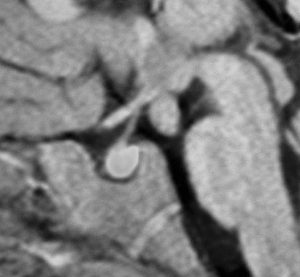

小さな典型的な視床下部過誤腫

無症候で発見されたpedunculated typeです。視床下部の底面からぶら下がるようにしてあります。左のCISS画像で形がよくわかります。中央のT1では灰白質と等信号です。右のT2では高信号となっています。

乳頭体(矢印)からは離れているタイプです。ですから笑い発作を生じません。右側のガドリニウム増強画像ではまったく増強されていないのが特徴です。